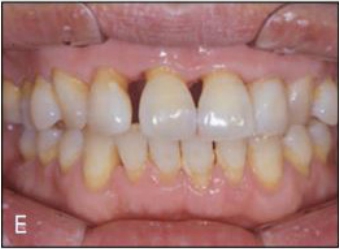

[증례] 치주질환으로 심한 병적 치아이동(pathologic tooth migration, PTM)이 나타나 기능적, 심미적 회복을 위해 교정을 한 65세 고령 환자 증례. 전악 치근단사진에서 볼 수 있듯이 전치 뿐 아니라 구치부 전 치아에 걸쳐 심한 염증이 발생하고 이로 인해 구치부에서도 PTM 이 심하게 나타나 치주치료 후 구치 교합이 불안한 상태가 초래 된 환자이었다.

치주치료 후 보철의사에게 돌아온 환자의 교합을 보고 dual bite 상태에서는 보철을 할 수 없는 바, 치주질환 이전의 교합 상태로의 교정을 의뢰하였다. 전체적으로 치주지지가 불량하여 움직일 치아만 제대로 움직 이는 치료가 매우 어려운 케이스이기 때문에 기공비용이 다소 많이 들지만 간단하게 치료 할 수 있는 투명교정장치를 사용하여 치료하기로 하였다. 구치부의 경우 협측전위된 우측 제1, 제2소구치와 좌측 제1소 구치 이동을 위해 투명교정장치를 사용할 경우 다수의 장치가 필요할 것으로 생각되어 대구치를 고정원으로 하여 소구치를 간단 하게 이동시키는 TPA 장치를 이용하였으며, 이후 투명교정장치로 전치부 공간을 클로져하여 간단하게 교정을 마무리 하였다(그 림 23-5, 6).